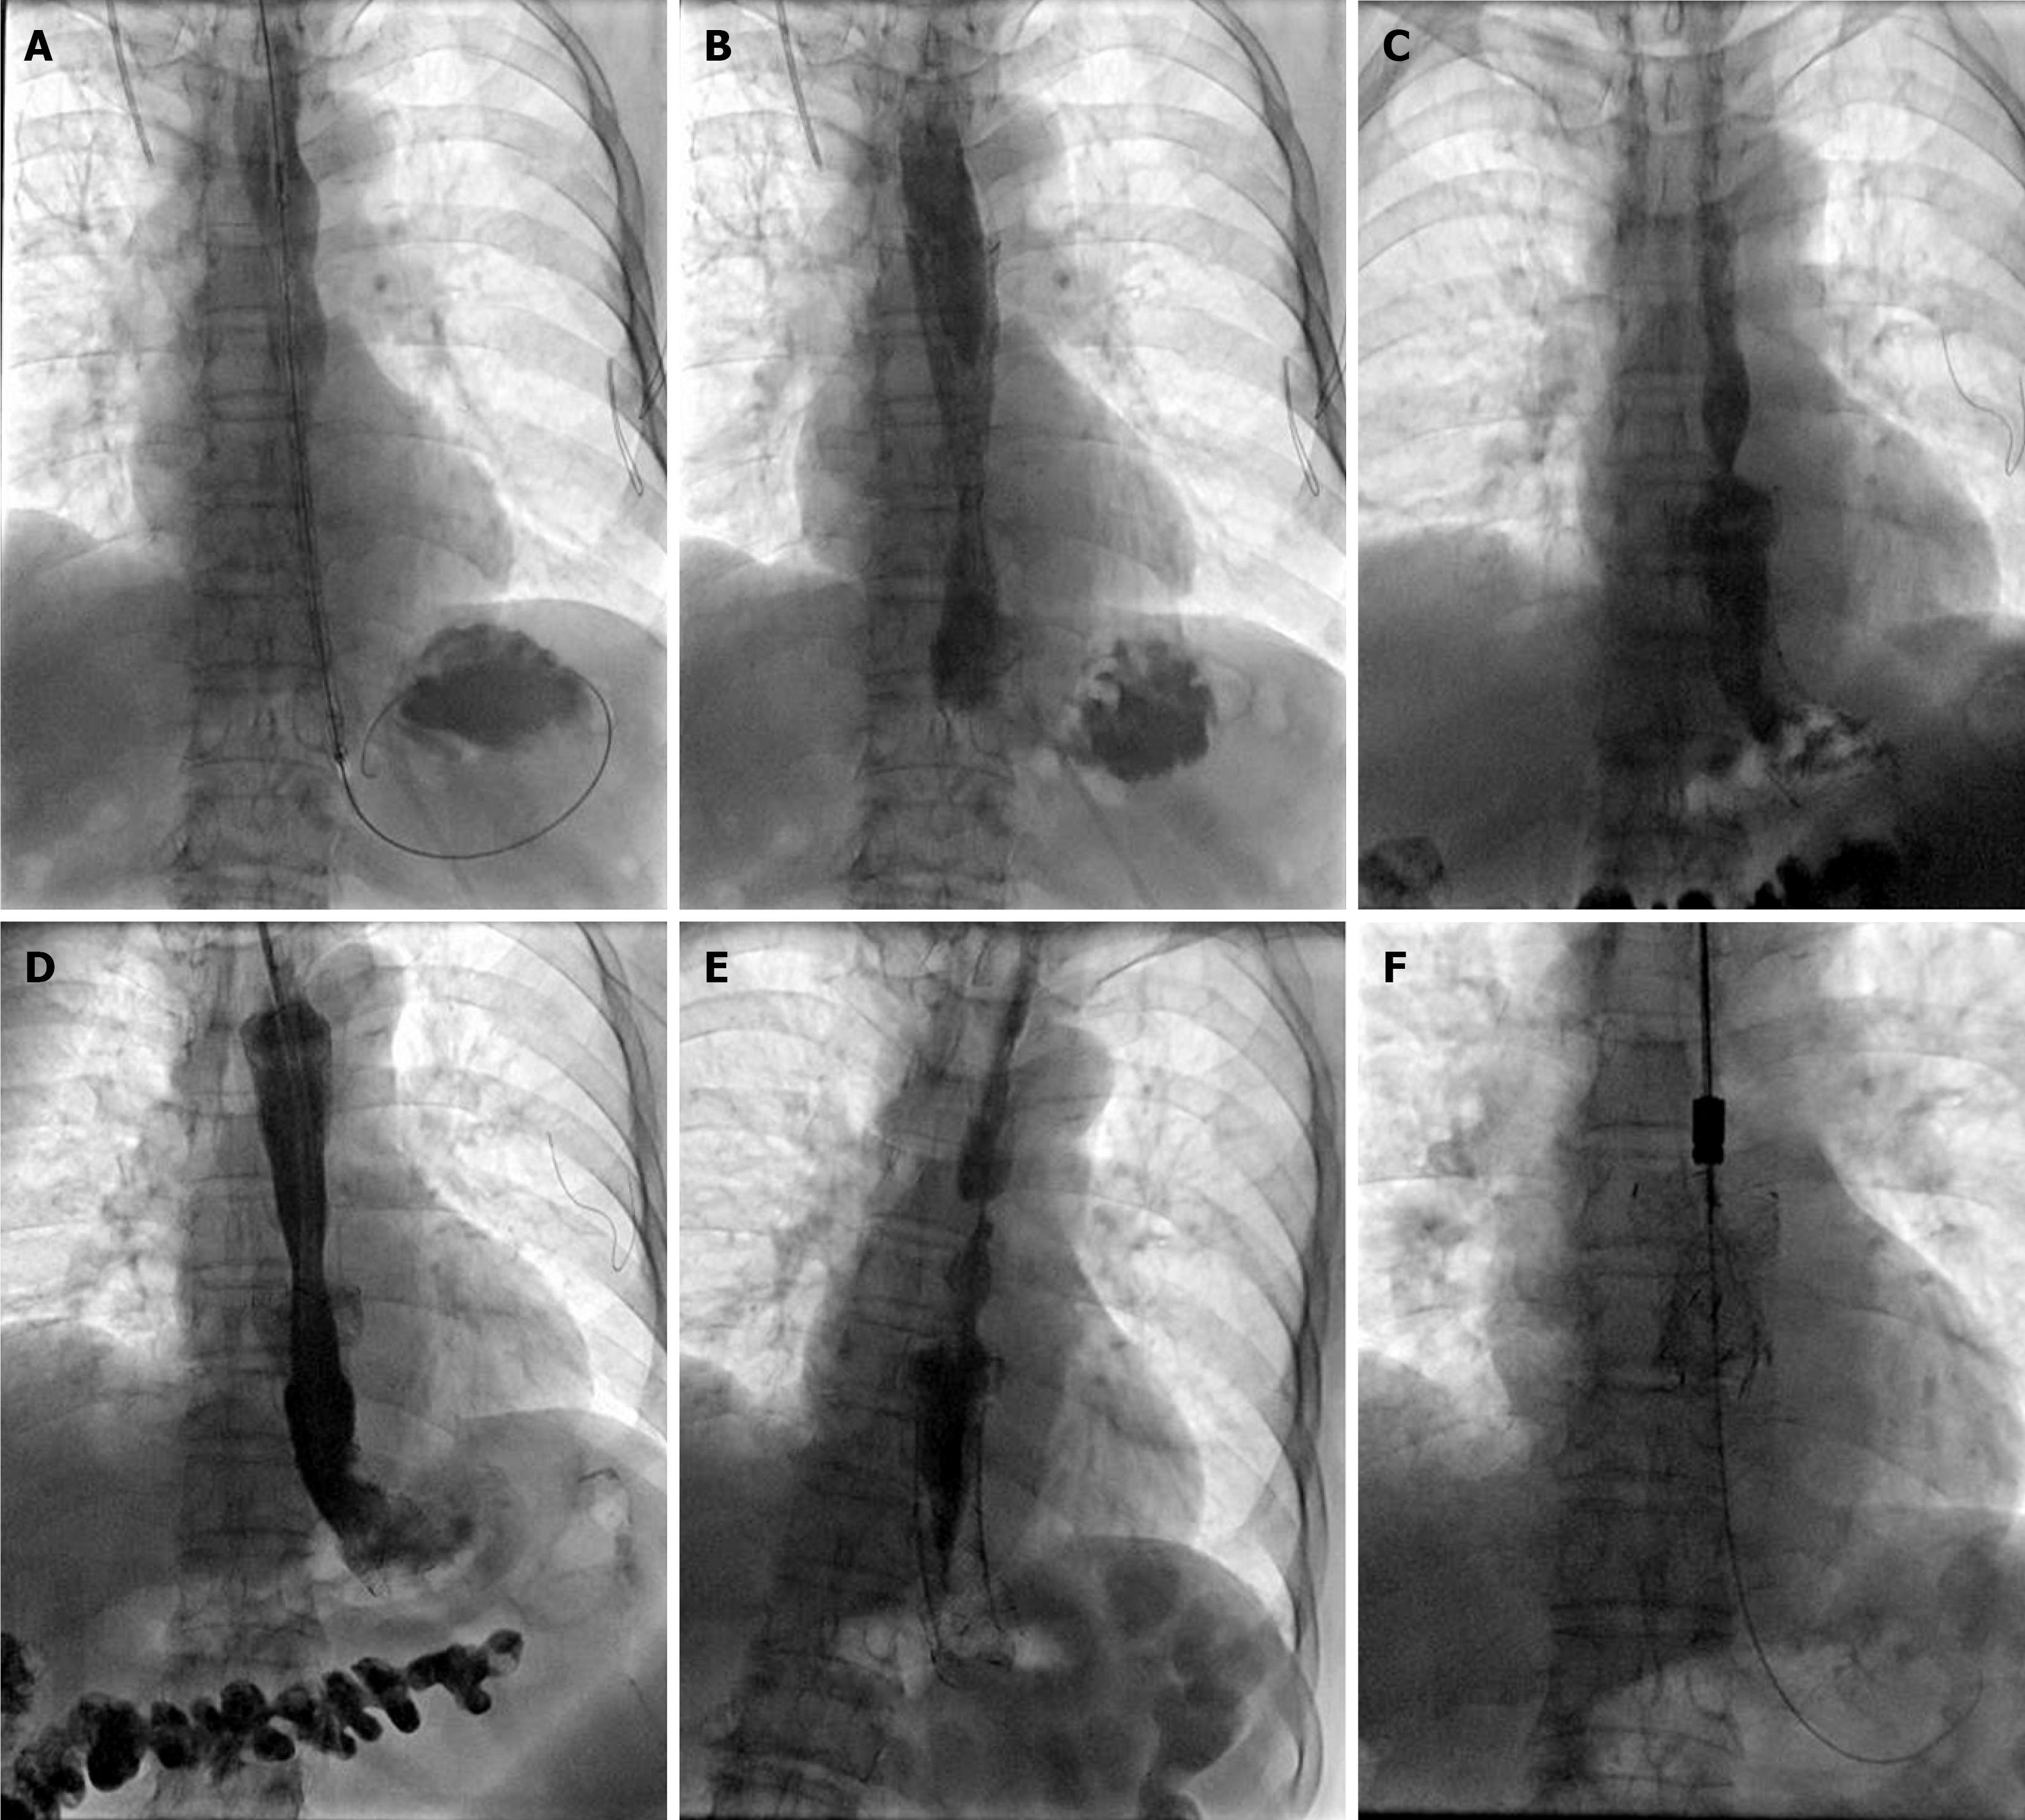

Figure 4 Fluoroscopically guided stenting procedure for the senile patient.

A: A 20 mm × 120 mm oesophageal stent was introduced and inserted in the lower esophagus; B: The oesophagogram immediately after the procedure shows improved passage through the widened lumen of the lower esophagus; C: Restenosis was observed at the proximal end of the stent 2.5 months after stent placement; D: A second 20 mm × 100 mm oesophageal stent was implanted at the stricture site; E: The second stent migrated distally about 2 months after placement, leading to symptom recurrence; F: The two stents were successfully removed under fluoroscopy.